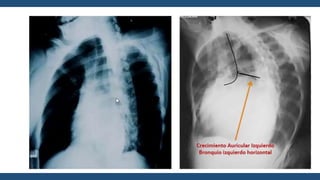

Radiografía de

Tórax

• Corazón generalmente de tamaño normal

• Perfil izquierdo con 4 arcos

• Aorta

• Pulmonar abombada

• Orejuela Izquierda prominente

• Ventrículo Izquierdo Normal

• En posiciones oblicuas

hay crecimiento de la AI

• Signos radiológicos de

hipertensión venocapilar

Moteado difuso

Hilios Pulmonares

Esfumados

Lineas A de Kerley

Lineas B de Kerley

Derrame Laminar

Infiltrados algodonosos

Guadalajara, J. F. (2012). Cardiología. CDMX: Mendez Editores.

Radiografía de Tórax • Corazóngeneralmente de tamaño normal • Perfil izquierdo con 4 arcos • Aorta • Pulmonar abombada • Orejuela Izquierda prominente • Ventrículo Izquierdo Normal • En posiciones oblicuas hay crecimiento de la AI • Signos radiológicos de hipertensión venocapilar Moteado difuso Hilios Pulmonares Esfumados Lineas A de Kerley Lineas B de Kerley Derrame Laminar Infiltrados algodonosos Guadalajara, J. F. (2012). Cardiología. CDMX: Mendez Editores.